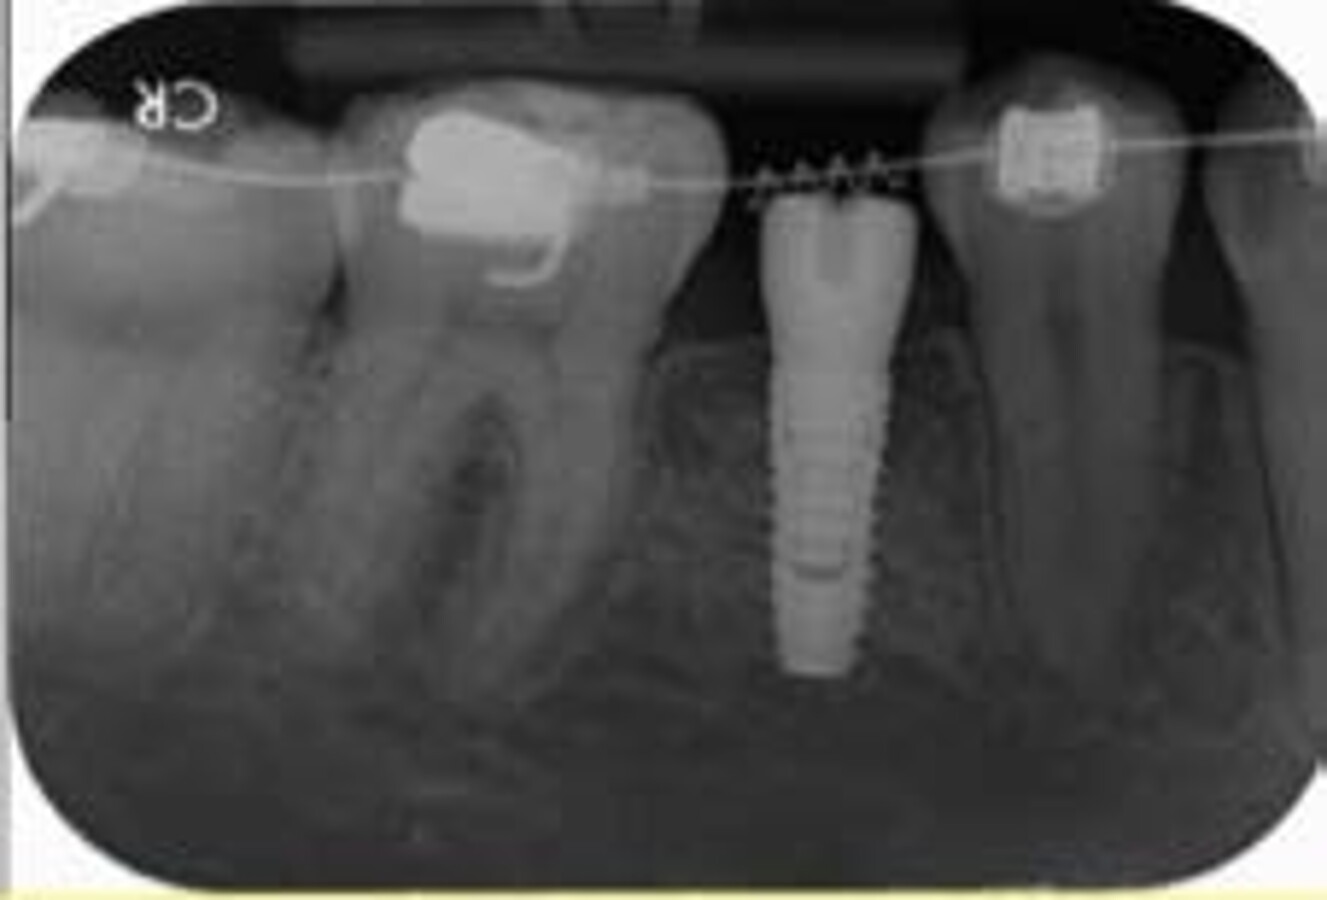

Fig. 5: Five-year post-op IOPA showing stable bone levels

Key radiographic measurements:

- Implant angulation

- Crown design (straight, mesially, distally placed)

- Implant depth (equicrestal or subcrestal)

- Bone resorption levels

- Crown-to-implant ratio